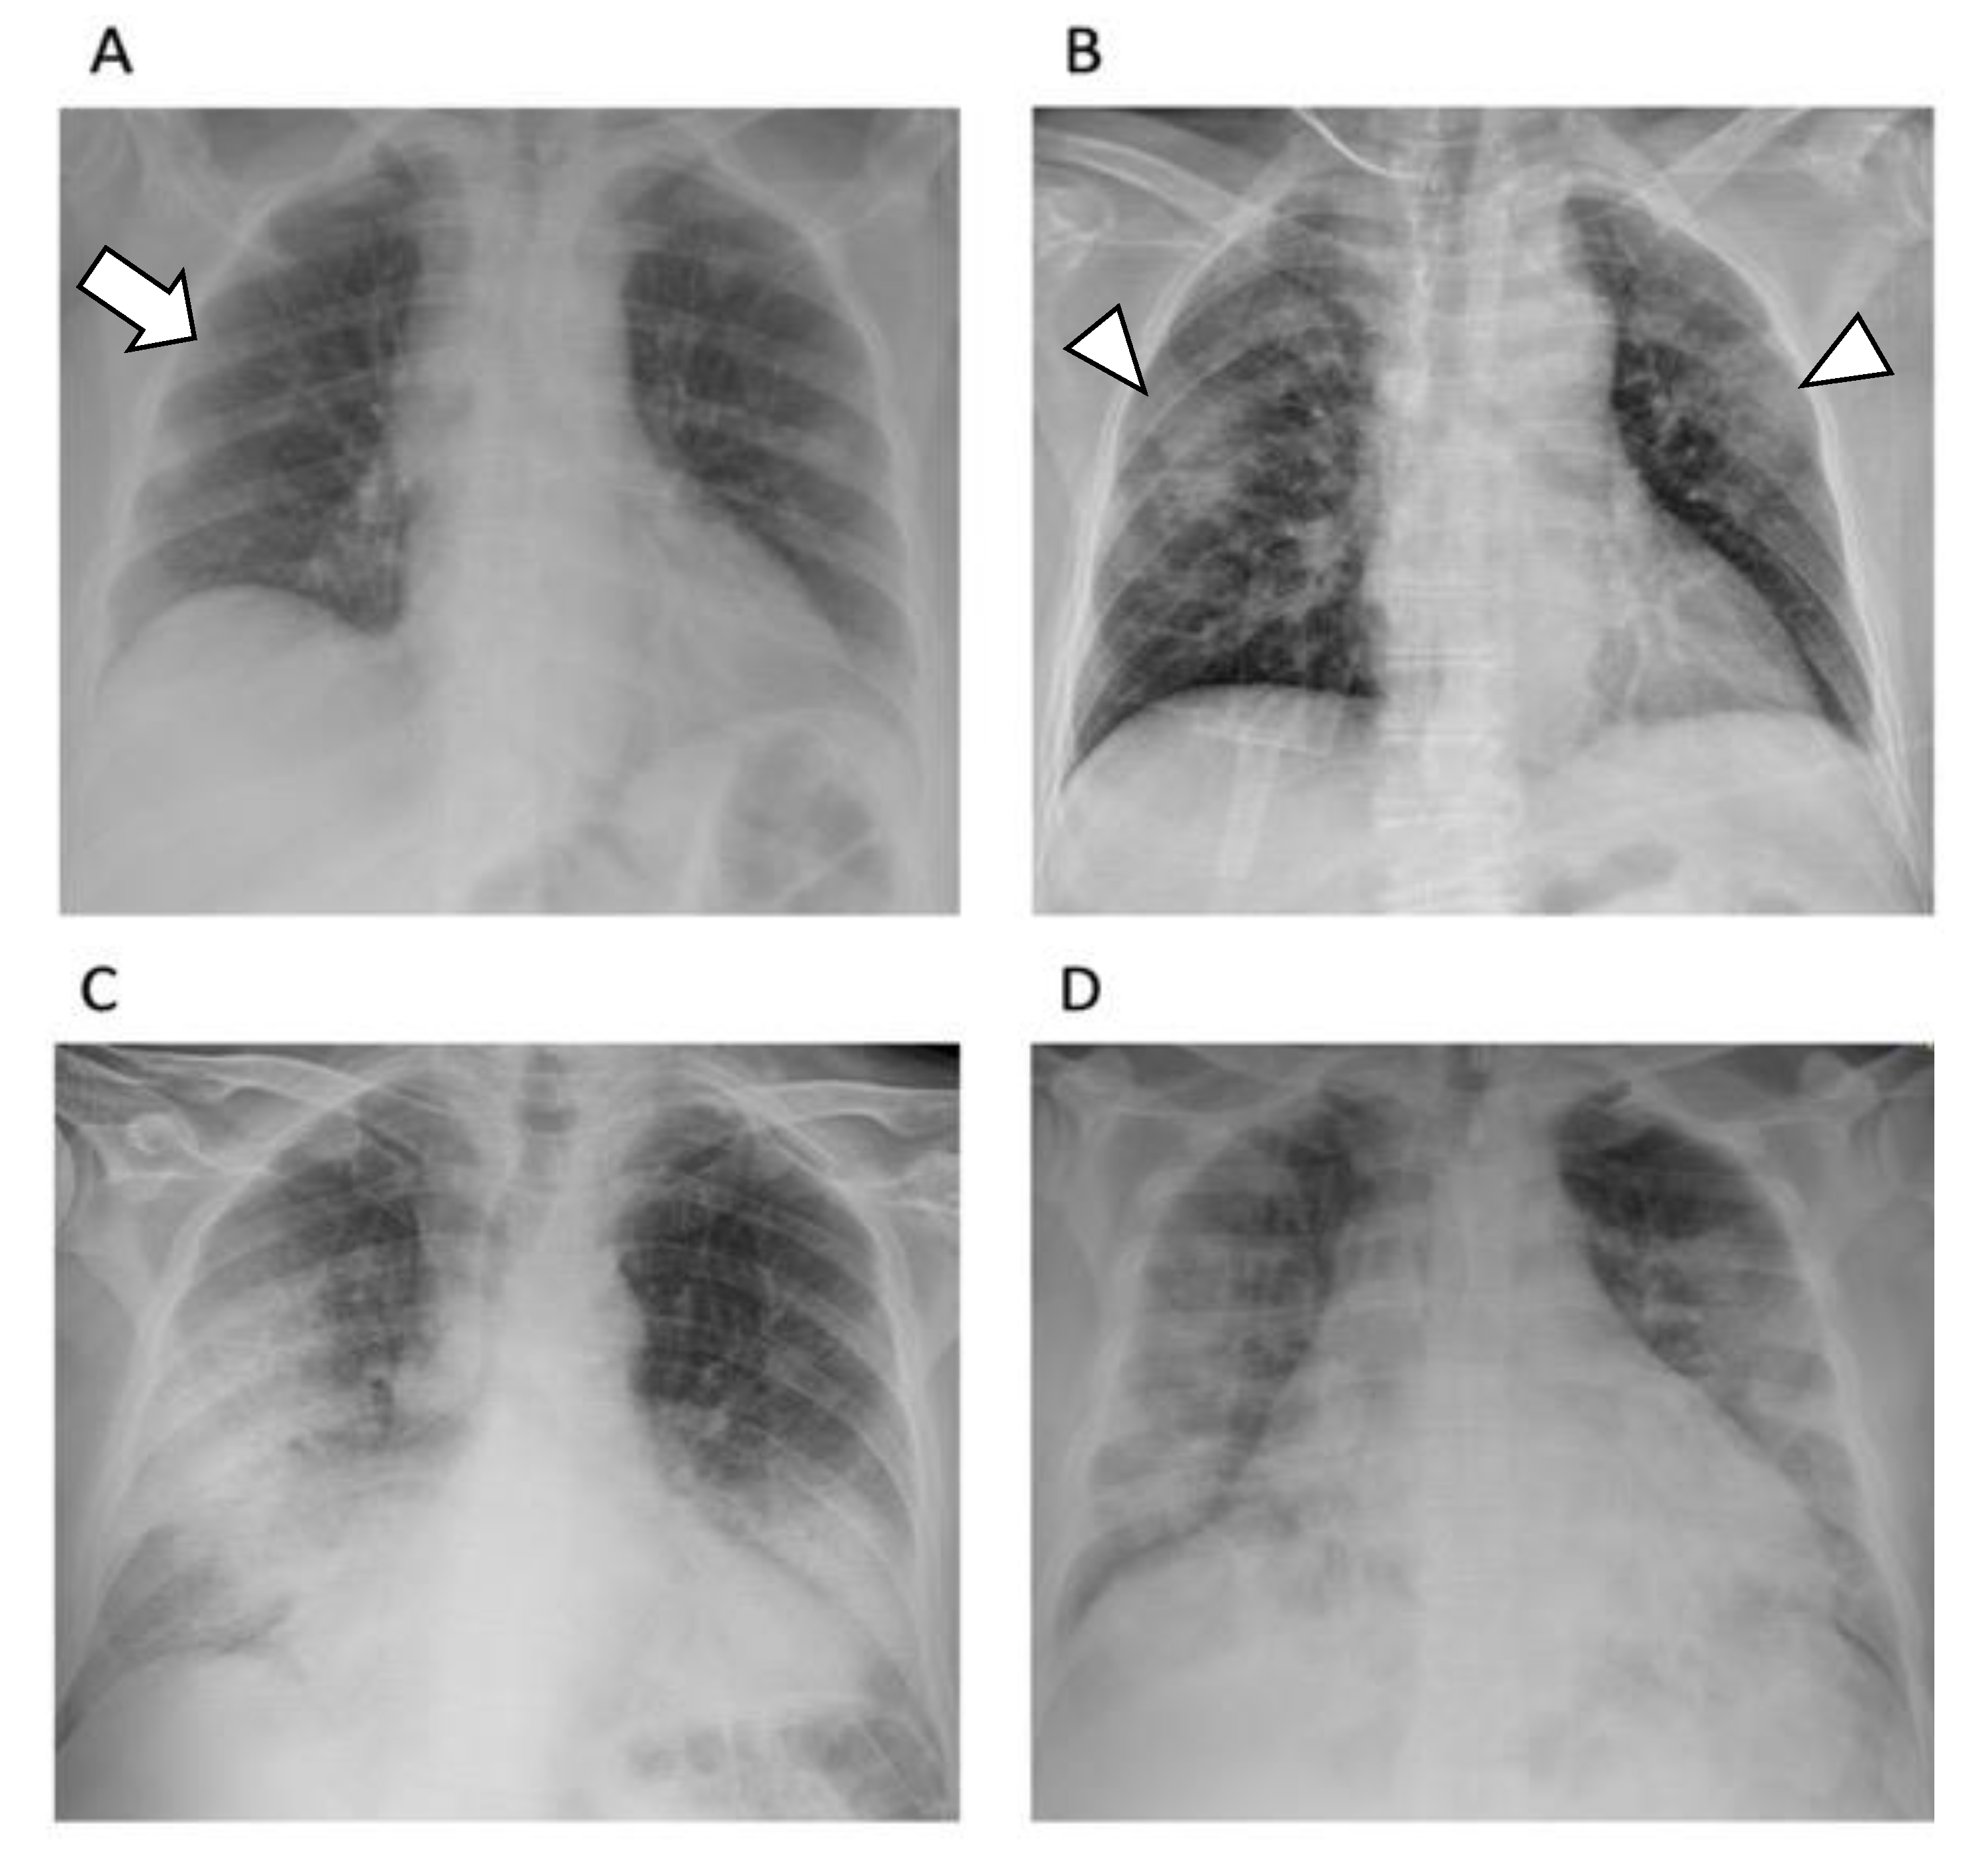

2.6. The Usefulness of Chest X-ray

- Vernuccio, F.; Giambelluca, D.; Cannella, R.; Lombardo, F.P.; Panzuto, F.; Midiri, M.; Cabassa, P. Radiographic and chest CT imaging presentation and follow-up of COVID-19 pneumonia: A multicenter experience from an endemic area. Emerg. Radiol. 2020, 27, 623–632. [Google Scholar] [CrossRef] [PubMed]

- Jacobi, A.; Chung, M.; Bernheim, A.; Eber, C. Portable chest X-ray in coronavirus disease-19 (COVID-19): A pictorial review. Clin. Imaging 2020, 64, 35–42. [Google Scholar] [CrossRef]

- Wong, H.Y.F.; Lam, H.Y.S.; Fong, A.H.-T.; Leung, S.T.; Chin, T.W.-Y.; Lo, C.S.Y.; Lui, M.M.-S.; Lee, J.C.Y.; Chiu, K.W.-H.; Chung, T.W.-H.; et al. Frequency and Distribution of Chest Radiographic Findings in Patients Positive for COVID-19. Radiology 2020, 296, E72–E78. [Google Scholar] [CrossRef] [Green Version]